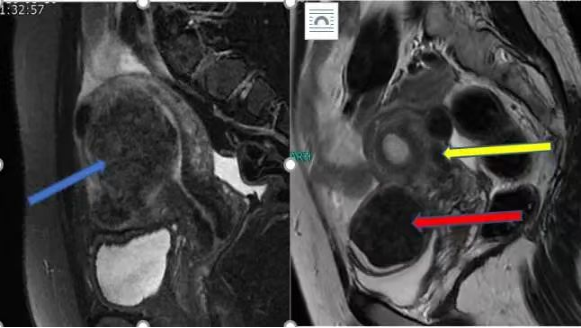

确实,过去我们检查子宫肌瘤,都选择价格便宜且快捷的超声。在确诊子宫肌瘤这方面占据了不可或缺的地位,对于一般没有症状的子宫肌瘤患者,超声检查仍然是首选的手段。 但是,对于有症状的子宫肌瘤患者,以及需要评估子宫肌瘤是否影响生育的患者,更推荐做磁共振检查。 磁共振检查可以获取整个盆腔的信息,可以从不同角度了解子宫及子宫肌瘤的情况。从而清楚的知道每个子宫肌瘤在什么位置上,是哪个肌瘤引起的临床症状,这个肌瘤如果继续长大,会不会对生育有影响等等问题。 磁共振检查能够辅助判断一个病灶是良性的还是恶性子宫肌瘤。 对于现在采用的一些微创手术如腹腔镜,在术前进行磁共振评估,能更好设计子宫上切口,从而最合适的切口进行子宫肌瘤的剔除。 左图蓝色箭头所示粘膜下肌瘤,右图红色箭头所示浆膜下肌瘤,黄色箭头所示肌壁间肌瘤,都能在磁共振上清楚的显示出来。 此图红色箭头所示为子宫肉瘤,磁共振清晰可见病灶范围,大小。 因此,对于子宫肌瘤治疗方式的选择,怀孕前评估子宫肌瘤对生育的影响,术前进行磁共振检查都是值得的。 九江市第一人民医院开发区分院/柯炜